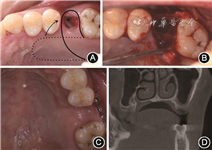

(5)治疗过程:①一期手术,见图2。术前设计腭侧旋转瓣(图2A)。抽取患者静脉血20 ml,离心(Medifuge MF200离心机,Silfradent,意大利)制备浓缩生长因子(concentrated growth factors,CGF)。患者取仰卧位,口内外消毒,铺巾。局部浸润麻醉后,牙槽窝内搔刮清创、暴露骨面,显露上颌窦底骨缺损(图2B)。先置入1张CGF膜至牙槽窝底,再置入明胶海绵,最后覆盖1张CGF膜在牙槽嵴顶。腭侧取约10 mm×25 mm大小带蒂半厚瓣,旋转至牙槽嵴顶封闭牙槽窝洞口,行严密缝合。一期手术术后3个月,26牙槽嵴顶黏膜愈合良好,颊侧角化龈充足,上腭转瓣区域愈合良好(图2C)。锥形束CT示牙槽窝内有新骨形成,骨高度约3 mm;上颌窦底骨板连续,黏膜厚度降低(图2D)。②二期手术,取静脉血20 ml,离心制备CGF。必兰局部浸润麻醉,于术区行梯形切口,翻开颊侧瓣,暴露骨面,采用超声骨刀于上颌窦外侧壁开约5 mm×10 mm大小骨窗,完整剥离上颌窦黏膜。置入CGF膜覆盖上颌窦黏膜,上颌窦内植入0.75 g异种骨移植物(Bio-Oss®,Geistlich Pharma AG,瑞士)。逐级备洞,植入软组织水平种植体(Straumann SLA®,Straumann,瑞士)4.8 mm×10 mm 1枚,初期稳定性为15 N·cm。于种植体颊侧颈部植入0.25 g异种骨移植物,覆盖1张可吸收胶原膜(Bio-Gide®,Geistlich Pharma AG,瑞士)13 mm×25 mm,严密埋入式缝合(图3)。